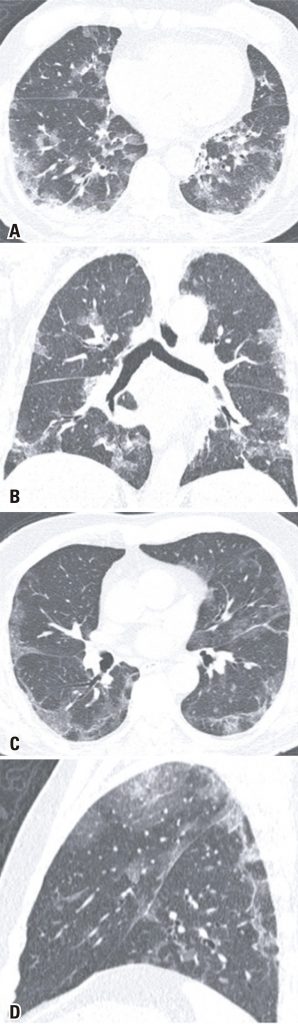

A COVID-19 foi declarada uma pandemia no início de 2020. Constatou-se, inicialmente, que as principais manifestações desse novo vírus ocorrem por meio de sintomas respiratórios e constitucionais. A tomografia do tórax foi eleita o exame de imagem para avaliar a extensão do comprometimento pulmonar e como um fator preditivo do prognóstico para a doença. No entanto, à medida que novos estudos são produzidos, o envolvimento gastrointestinal da COVID-19 torna-se mais evidente, com relatos de pacientes que manifestaram principalmente ou apenas sintomas gastrointestinais no decorrer da doença. Em alguns casos, a investigação inicial é realizada no pronto-socorro, com tomografia computadorizada do abdome. Relatamos uma série de casos de dez pacientes que compareceram ao serviço de emergência da instituição com uma queixa principal gastrointestinal e foram submetidos inicialmente a uma tomografia computadorizada de abdome como primeira investigação. Embora a maioria dos pacientes não tenha apresentado alterações significativas nas imagens abdominais, eles apresentaram achados pulmonares visualizados nas bases pulmonares, que depois foram caracterizadas como achados pulmonares típicos de COVID-19 nas tomografias de tórax subsequentes. Apenas um paciente apresentou achados atípicos para COVID-19 na tomografia. Todos os pacientes tiveram reação em cadeia da polimerase em tempo real positiva para o novo coronavírus. É muito importante alertar os radiologistas, principalmente os radiologistas abdominais, da possibilidade de sintomas gastrointestinais isolados no contexto da COVID-19. Além disso, deve ser um hábito para todos os radiologistas avaliar as bases pulmonares nas tomografias de abdome, local comumente afetado pela COVID-19.